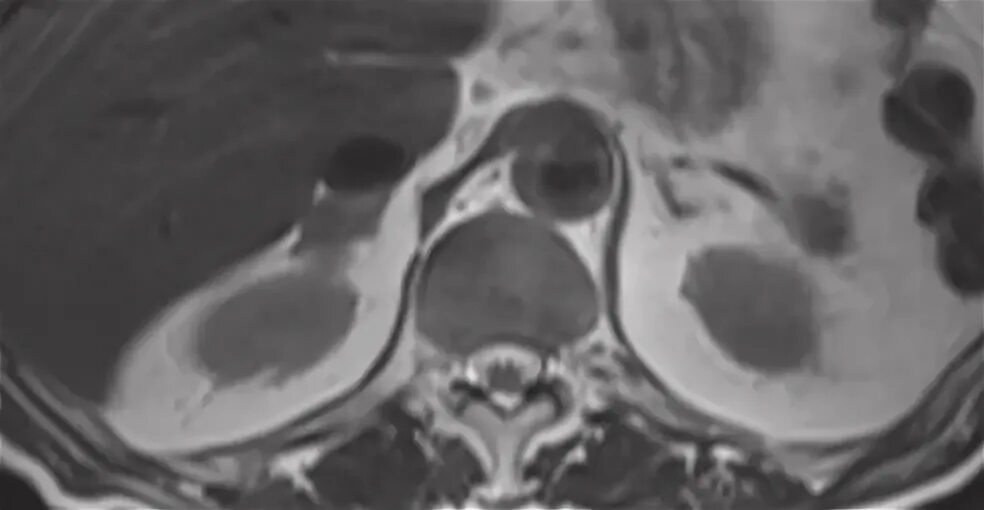

Обследование почек мрт